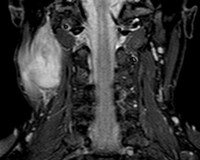

MRI of the soft tissues of the neck.

МРТ мягких тканей шеи. Метод сканирования шеи в постоянном магнитном поле с серией цифровых изображений и генерацией трехмерного изображения. Он используется для диагностики воспалительных и опухолевых процессов в органах и тканях шеи, при подозрении на травматическое повреждение и при наличии неметаллических инородных тел в гортани и трахее. Исследование проводится для выявления врожденных аномалий развития. Кисты могут быть необходимы для подготовки к операции на органах шеи. МРТ реже используется для оценки распространенности патологических процессов в щитовидной железе. Обследование является нативным или высококонтрастным, что особенно важно при диагностике опухолей. Процедура неинвазивная, проводится амбулаторно и в стационаре.